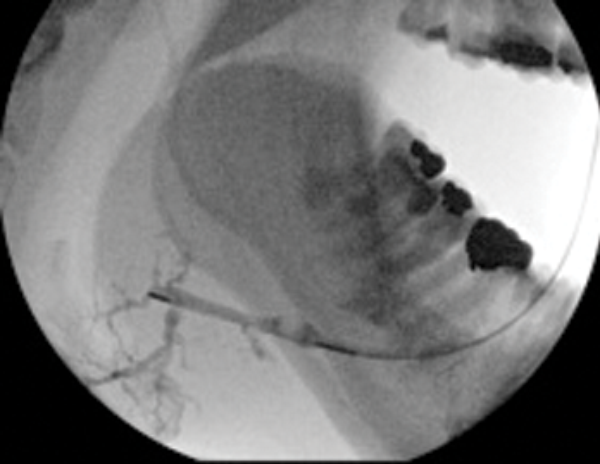

Figure 3: (A) The preoperative sialogram identifying a stone in the middle third of the submandibular duct.

Figure 3: (B) The insertion of a Dormia basket (closed).

Figure 3: (C) The stone trapped in the open basket.

Treatment of salivary calculi by interventional sialography

Miniature Dormia baskets can be inserted into the major salivary ducts under x-ray or ultrasound guidance and manipulated to pass and grasp small stones. The procedure is performed under local anaesthesia (by direct infiltration of the buccal oral mucosa or inferior dental nerve block). The trapped stone is then withdrawn to the duct ostium, where a small relieving papillotomy incision may be needed to release the stone. It is important to maintain regular salivary flow through a papillotomy site, if this has been necessary to release a stone during extraction in a Dormia basket, in order to prevent healing over of the duct orifice. This may be done by prescribing regular hydration and use of sialogogues, assisted by gland massage.

Case selection is best performed on the basis of preoperative sialography. Ideally the stone should be within the main extraglandular duct, mobile and no more than 20-25% wider than the distal duct running from stone to ostium [12].

Duct strictures lying between the stone and duct orifice may require dilatation by balloon ductoplasty but should always be viewed with caution as they are invariably densely fibrotic and may still impede stone removal.

Success in clearance of stones using Dormia baskets is reported to range from 60-100%. This technique therefore offers a simple, effective, highly non-invasive cure which is achievable in one visit with minimal morbidity. In avoiding general anaesthesia it offers treatment options to patients with other more serious co-morbidities.